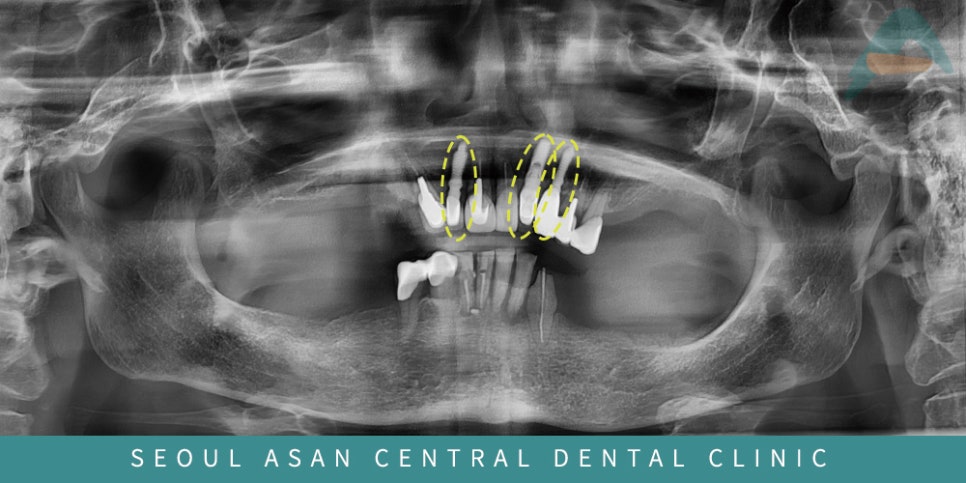

어금니쪽의 치아가 거의 상실된 상태였고,

남아있는 치아들도 전반적으로 치주 상태가 좋지 않아

흔들리는 치아도 다수이며,

염증소견이 있는 치아도 관찰되었는데요.

이런 경우, 상담을 통해 살릴 수 있는 치아를 제외하고는

나머지 치아는 발치 후 임플란트가 필요할 수 있습니다.